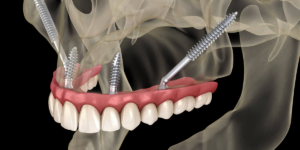

“I had all 32 teeth removed and 20 implants placed in just three hours,” the patient said. He was impressed by Dr. Vivek Gaur’s professionalism and soundness, especially in managing his intricate medical history. In just one year, the transformation was evident. The patient regularly returns for check-ups, noting that while minor adjustments to his bite were necessary, the implants have been stable and comfortable.

The visual impact of full mouth reconstruction is life-changing. You can get the best dental implants in Delhi NCR at Dr. Vivek Gaur’s clinic in Indirapuram, Ghaziabad.

The patient’s journey is a testament to Dr. Vivek Gaur’s skills in performing complex surgeries with minimal discomfort. While undergoing a procedure of such magnitude—32 teeth extractions and 20 implants—the results are evident within a short span. Patients not only regain their ability to eat and speak comfortably but also experience a marked improvement in their appearance.